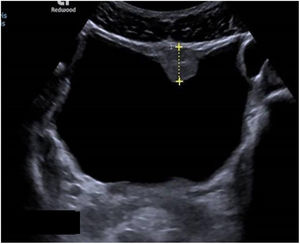

Las exploraciones radiológicas desempeñan un papel importante en el diagnóstico de la enfermedad y sus complicaciones9,29. La radiografía de abdomen puede mostrar principalmente calcificaciones en la pared de la vejiga (fig. 4). La ecografía es la exploración más rentable, permitiendo diagnosticar lesiones en vejiga urinaria como engrosamientos de la mucosa, nódulos (fig. 5), ureterohidronefrosis o la fibrosis periportal (fig. 6) con o sin hipertensión portal característica de la afectación hepatointestinal. Otras exploraciones como la TAC o la RMN pueden ayudar al diagnóstico, sobre todo en casos de localizaciones ectópicas como puede ser el pulmón o el sistema nervioso central. La tabla 2 muestra resumidas las características de las principales pruebas empleadas en el diagnóstico de la esquistosomiasis.